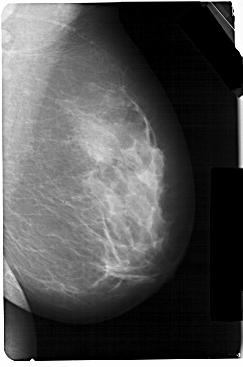

A_1301_1.RIGHT_CC

RIGHT_CC LINES 5356 PIXELS_PER_LINE 3451 BITS_PER_PIXEL 12 RESOLUTION 43.5 NON_OVERLAY